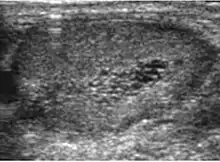

Seminoma is the most common tumor type in cryptorchid testes. The risk of developing a seminoma is increased in patients with cryptorchidism, even after orchiopexy. There is an increased incidence of malignancy developing in the contralateral testis too, hence sonography is sometimes used to screen for an occult tumor in the remaining testis. On US images, seminomas are generally uniformly hypoechoic, larger tumors may be more heterogeneous [Fig. 3]. Seminomas are usually confined by the tunica albuginea and rarely extend to peritesticular structures. Lymphatic spread to retroperitoneal lymph nodes and hematogenous metastases to lung, brain, or both are evident in about 25% of patients at the time of presentation.

Embryonal cell carcinomas, a more aggressive tumor than seminoma usually occurs in men in their 30s. Although it is the second most common testicular tumor after seminoma, pure embryonal cell carcinoma is rare and constitutes only about 3 percent of the nonseminomatous germ cell tumors. Most of the cases occur in combination with other cell types. At ultrasound, embryonal cell carcinomas are predominantly hypoechoic lesions with ill-defined margins and an inhomogeneous echotexture. Echogenic foci due to hemorrhage, calcification, or fibrosis are commonly seen. Twenty percent of embryonal cell carcinomas have cystic components. The tumor may invade into the tunica albuginea resulting in contour distortion of the testis [Fig. 4].